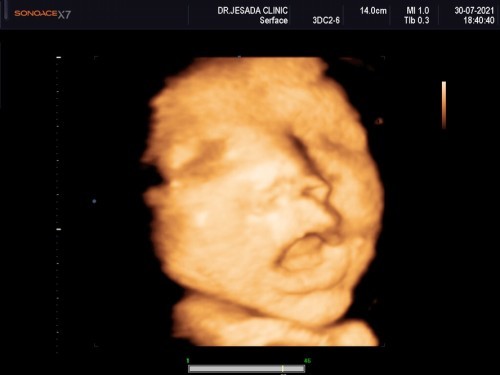

37Week ทีมสิงหาคม ❤️

น้องน้ำหนัก3070 กรัมแล้วค่ะ 😂